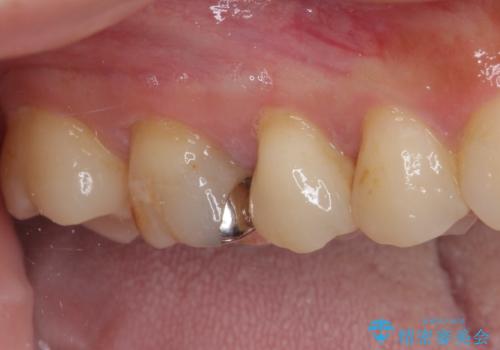

処置後に痛みを感じることはなく、冷たいものがしみることもなくなりました。

奥の大臼歯にもむし歯があったので、一緒に処置を行いました。